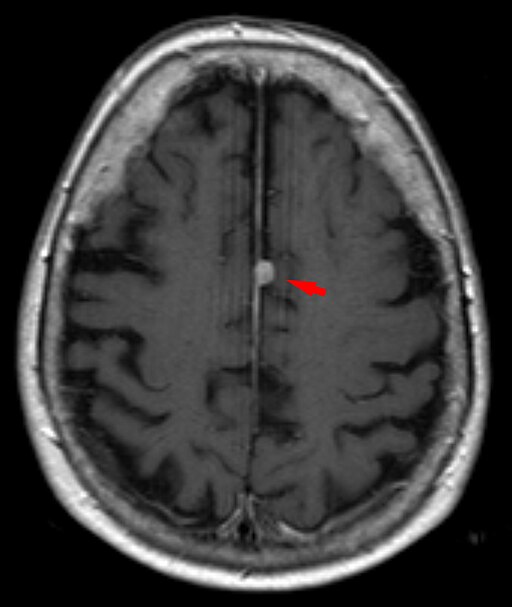

În figura următoare se vede un meningiom parasagital care captează intens contrast:

Hellerhoff, CC BY-SA 3.0

RMN axial T1 cu gadoliniu – se observă o formațiune rotundă bine delimitată pe linia mediană (săgeata roșie) care preia uniform contrast, tipic pentru meningiom. Tumora este atașată de dura și deformează ușor parenchimul cerebral adiacent. (Hellerhoff, CC BY-SA 3.0 <https://creativecommons.org/licenses/by-sa/3.0>, via Wikimedia Commons).

RMN-ul poate evidenția și efectul de masă (edem peritumoral, deplasarea structurilor cerebrale) și este util în planificarea tratamentului.